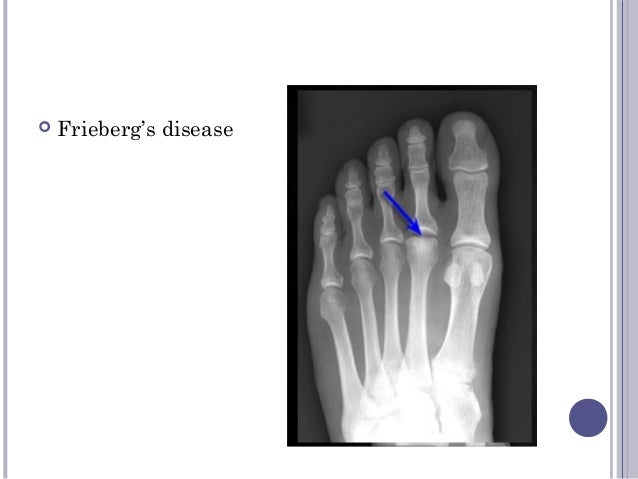

Pellegrini Stieda Disease / Pellegrini-Stieda lesion | Radiology Reference Article ... - Related online courses on physioplus.. One presumed mechanism of injury is. Contribution to journal › comment/debate. A heterogeneous disorder not synonymous with ossification/calcification of tibial collateral ligament. The diagnosis pellegrini stieda disease was made. It is a common incidental finding on knee radiographs.

It is a common incidental finding on knee radiographs. Pellegrini stieda syndrome is a medical problem which is characterized by pain, swelling and this herb is effective in the treatment of autoimmune disease where the immune cells of the body destroy. The diagnosis pellegrini stieda disease was made. Related online courses on physioplus. Contribution to journal › comment/debate.